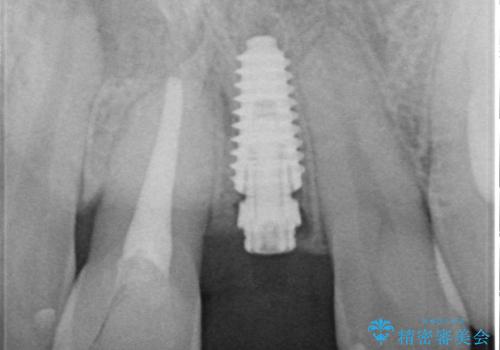

- 転倒により前歯を失ったところにインプラント治療を受けたいとのことで来院された患者様です。

転倒を機に矯正治療を行ったようで、歯列が整い、インプラントのスペースができたとのことで受診をされました。

骨量は十分にあったため、インプラント埋入後速やかに仮歯を装着して、歯肉治癒後にオールセラミッククラウンによる補綴治療を行うこととしました。